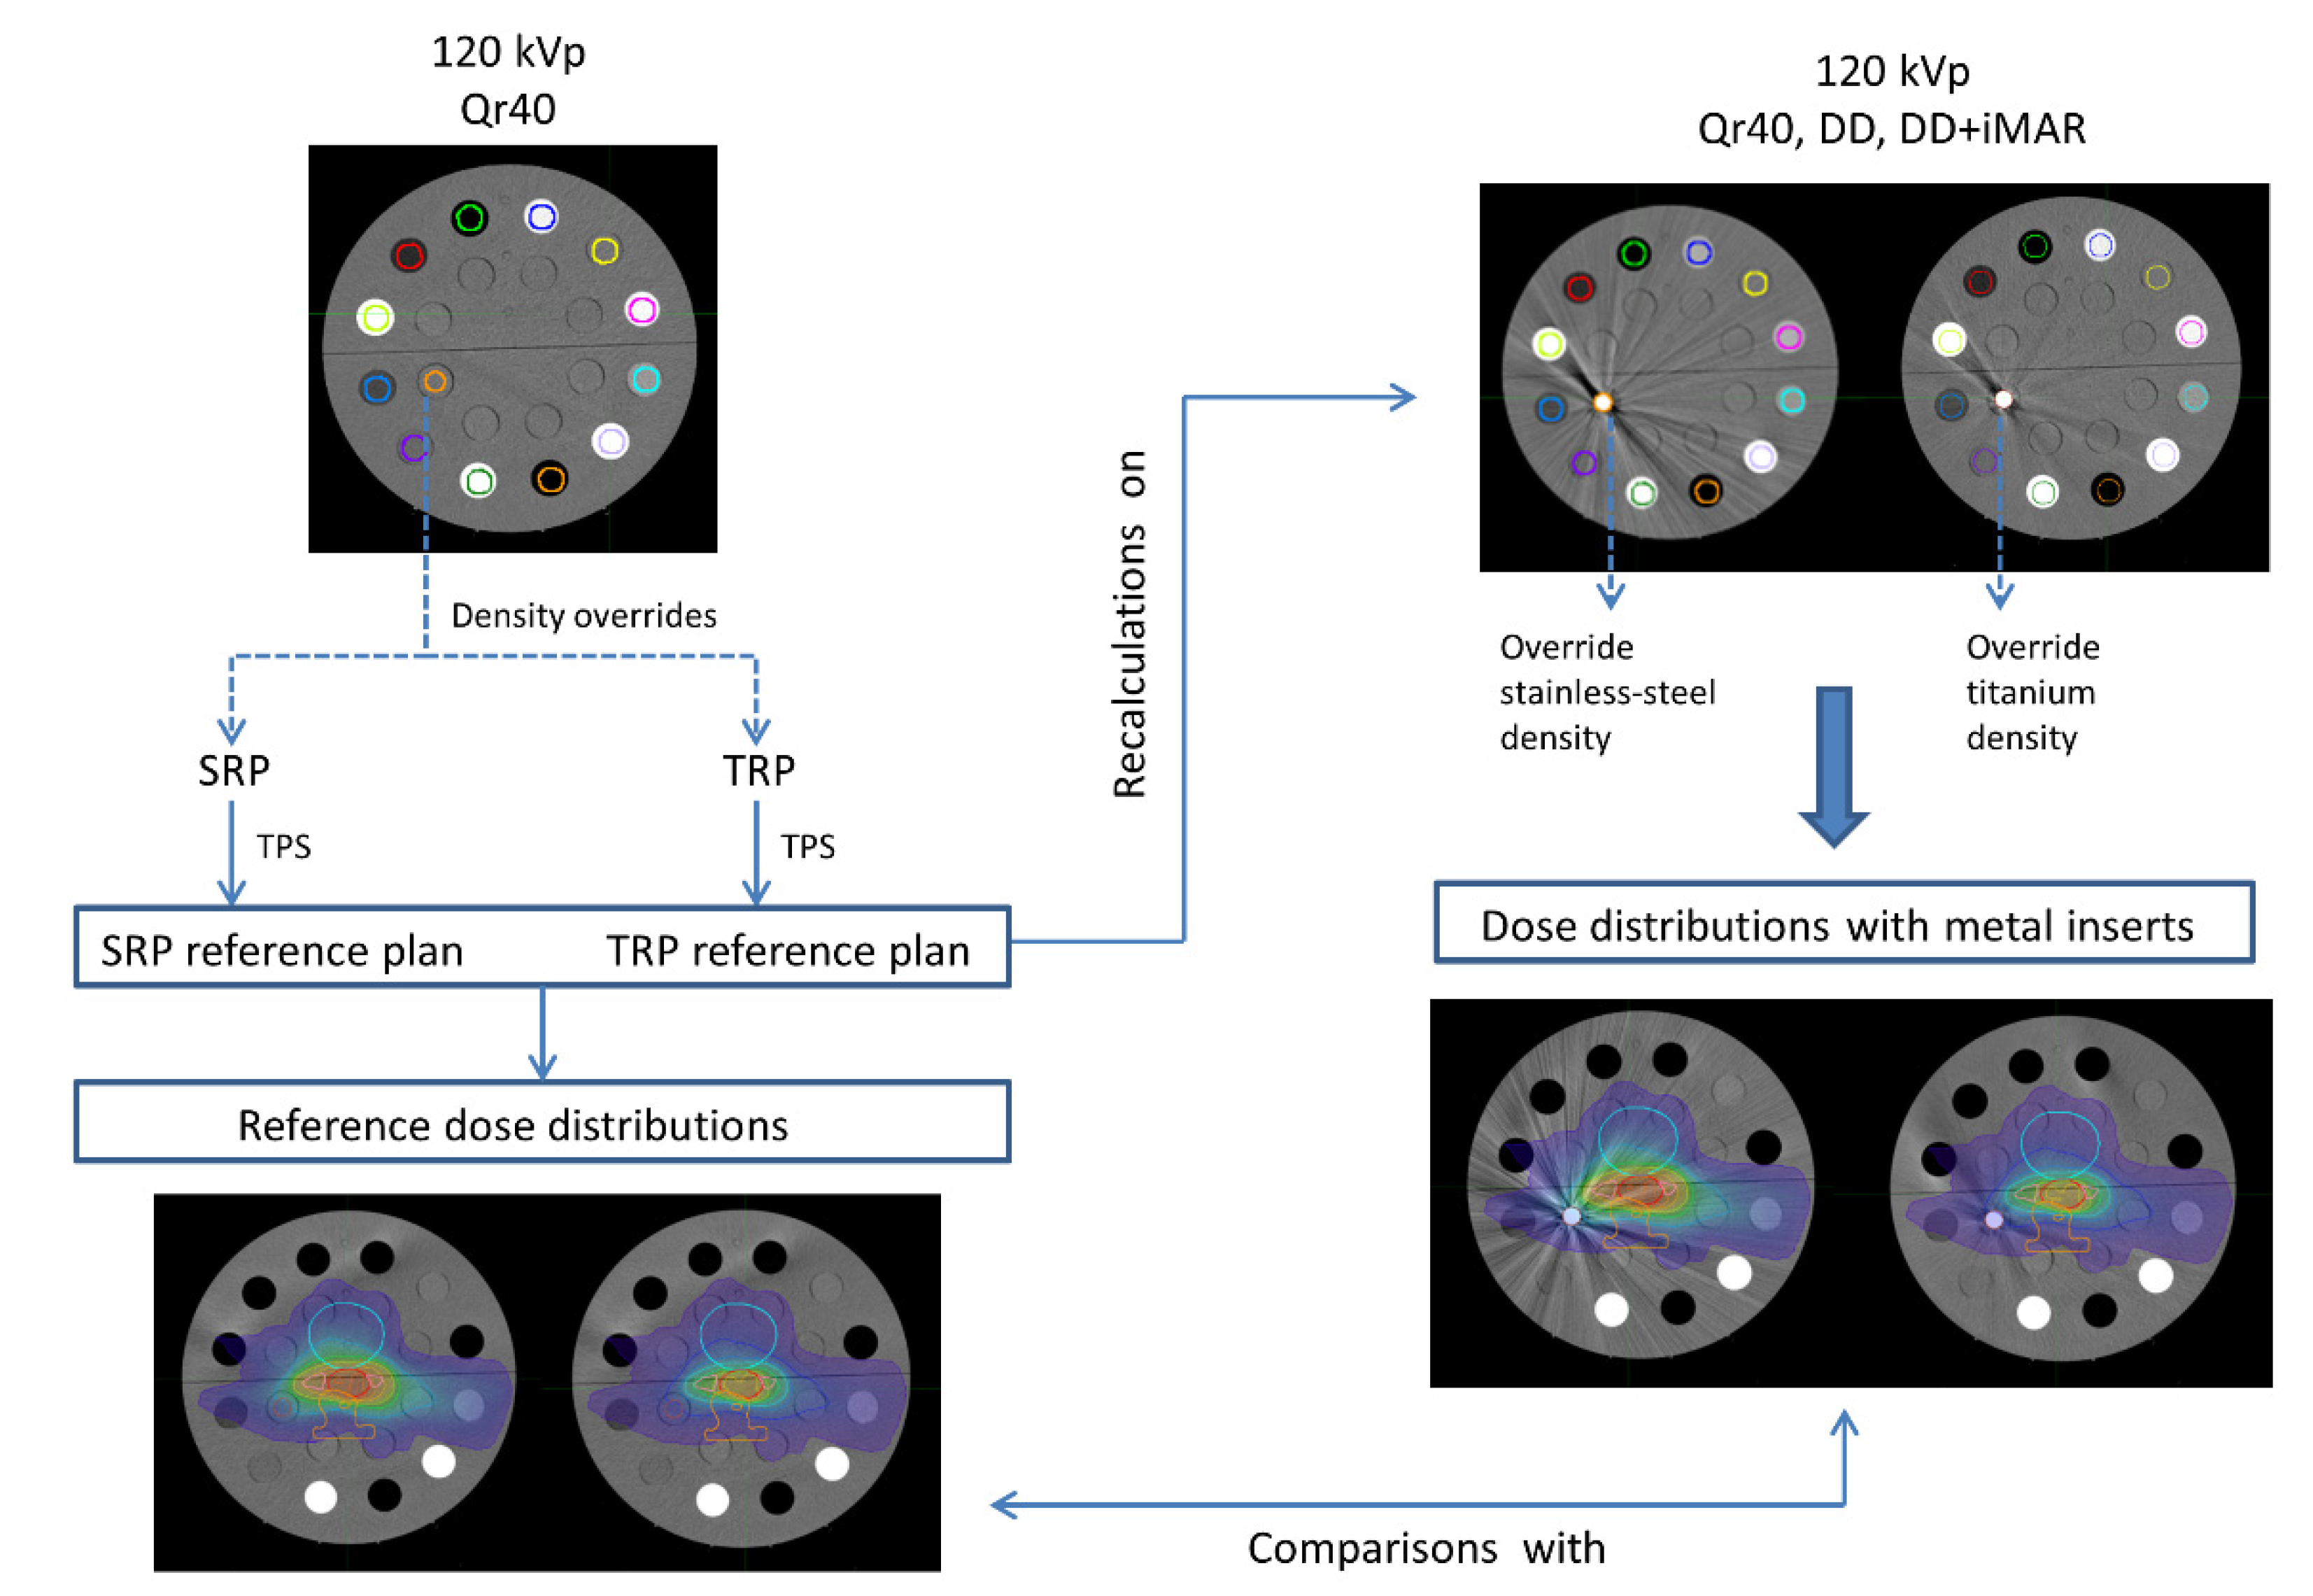

2.4. Dose Distributions

3.3. Dose Distributions